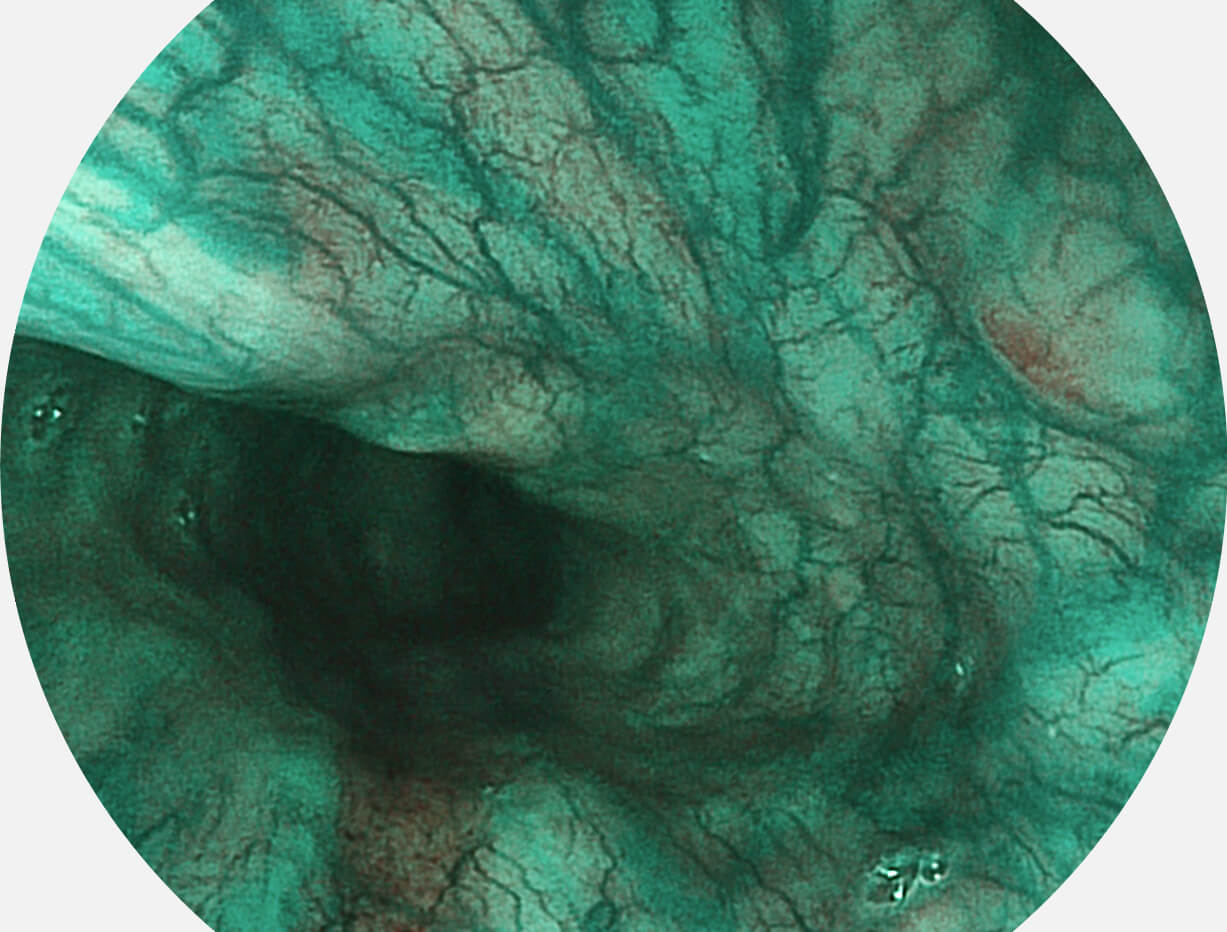

Spectral Focused lmaging, SFI

图像具有高亮度、高黏膜血管颜色对比度的特点,且不改变粘液、食物残渣、粪便的基本颜色,可在中远景下进行观察,助力消化道早期疾病的诊断。

SFI图像

白光图像